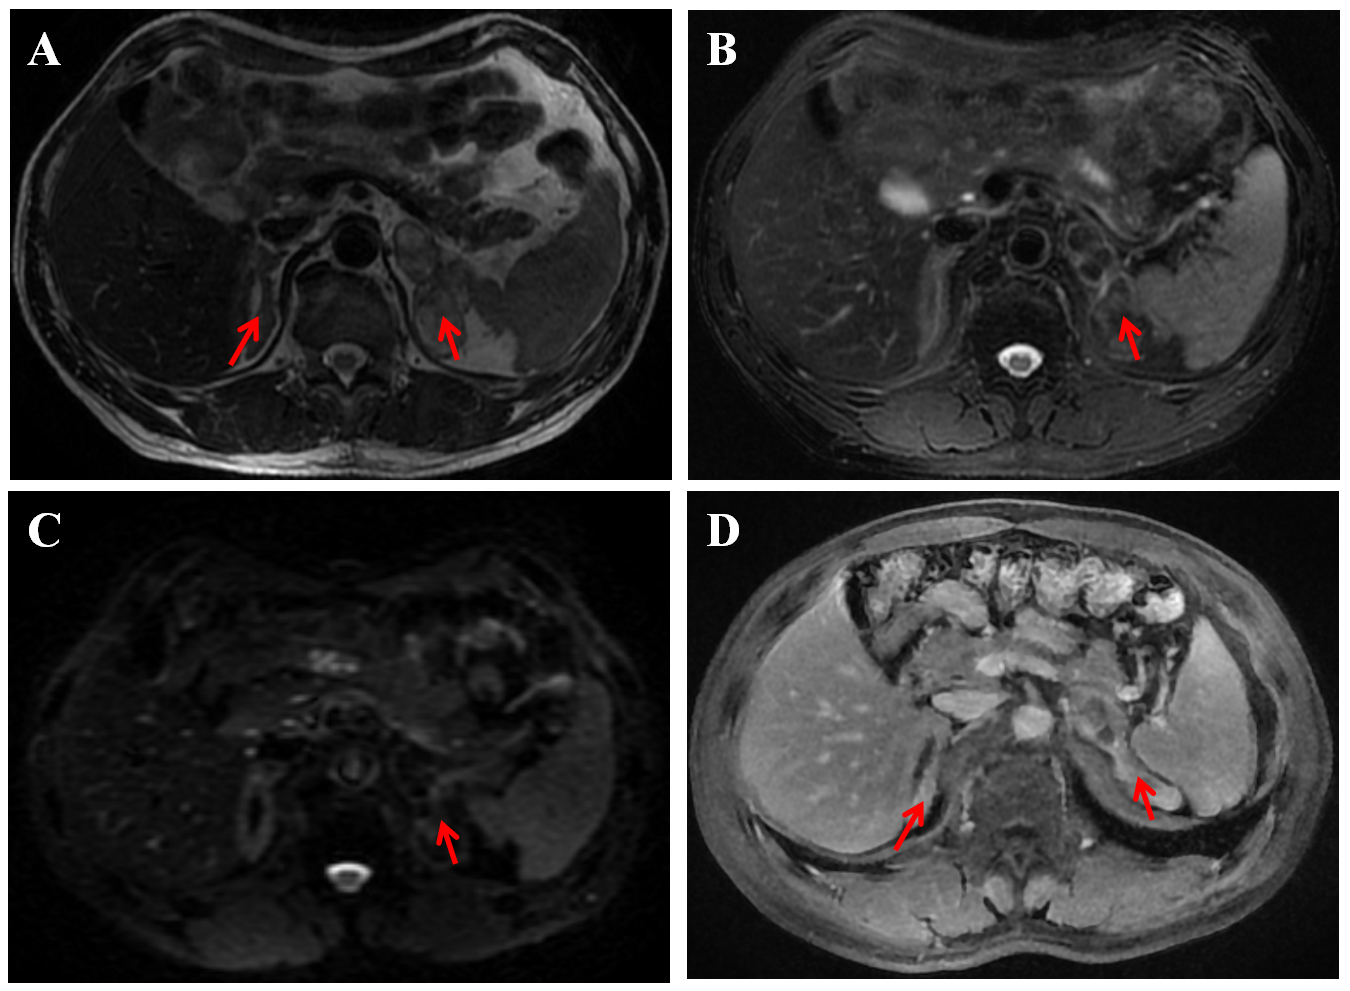

Additionally, enhanced magnetic resonance imaging (MRI) of the adrenal gland revealed multiple medullary lipomas in both the inner and outer limbs of the left adrenal gland, an adenoma in the outer limb of the left adrenal gland, and thickening of the right adrenal gland, consistent with adrenal hyperplasia (Fig. 3). No significant retroperitoneal lymphadenopathy was observed, and pituitary MRI did not reveal any apparent abnormalities. Based on these comprehensive clinical and imaging findings, a provisional diagnosis of CAH was established.

Fig. 3.

Enhanced magnetic resonance imaging of the adrenal gland. The report of the patient indicated multiple medullary lipomas within the inner and outer limbs of the left adrenal gland, an adenoma in the outer limb of the same gland, and thickening of the right adrenal gland, which is suggestive of adrenal hyperplasia. (A) On T2-weighted imaging (T2WI), the right adrenal gland is thickened and multiple abnormal masses in the left adrenal gland showed high signal intensity (the red arrows). (B) On the T2WI fat-saturated sequence, the left adrenal masses presented low signal intensity (the red arrow). (C) The diffusion-weighted imaging (DWI) signal was not high (the red arrow). (D) After contrast enhancement, the right adrenal gland showed obvious enhancement, and the left adrenal gland showed marginal enhancement (the red arrows).